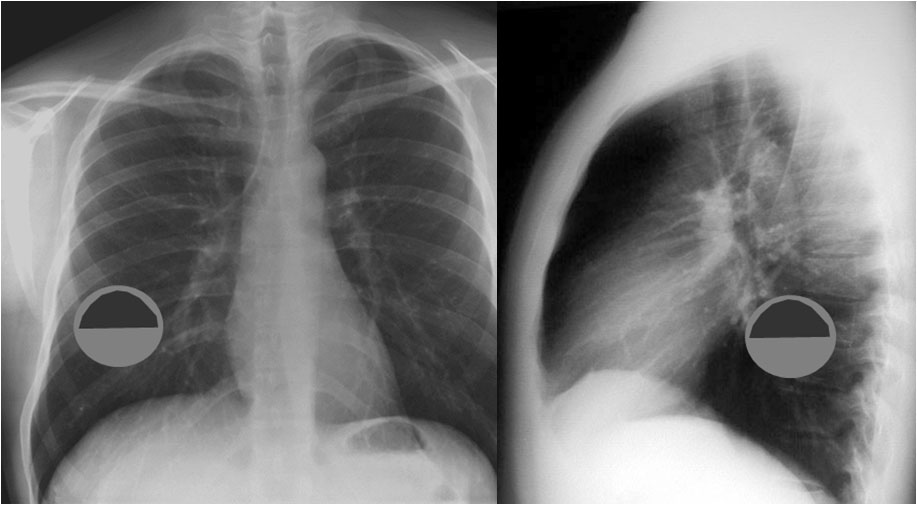

SIGNO DEL TUMOR FANTASMA O TUMOR EVANESCENTE

Signo que describe al derrame pleural atrapado en la cisura menor, especialmente en pacientes con insuficiencia cardiaca. El derrame loculado en la proyección posteroanterior se ve como una lesión nodular o masa que simula un tumor sólido (imagen superior). Sin embargo, la evolución rápida hacia la desaparición de esta lesión sugiere que se trata de derrame.

Vemos en las imágenes un tumor fantasma que desaparece en el control realizado cinco días más tarde.

En la primera imagen, la presencia de derrame pleural asociado y el engrosamiento del resto de la cisura menor, visible como una línea superpuesta al tumor fantasma, sugieren el diagnóstico.